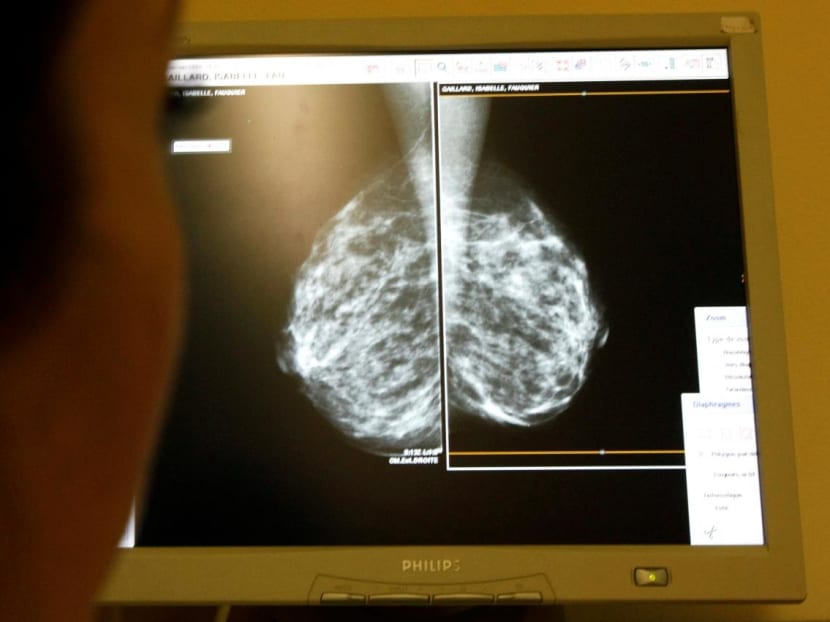

Or the importance of regular mammograms in helping us detect breast cancer early.

Breast cancer in stage 0 and 1 are more commonly detected through mammogram screening. Intuitively, breast cancer in stage 0 or 1 would have a much higher long-term cure rate than disease in in stage 2 or 3.

Unfortunately, less than 40 per cent of Singaporean women aged between 50 and 69 go for a mammogram.